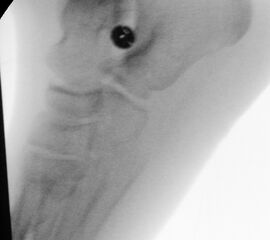

Diagnostisches Vorgehen

Damit die minimalinvasive Fußchirurgie zur Korrektur kindlicher oder jugendlicher Fußdeformitäten erfolgreich angewendet werden kann, erfordert die präoperative Diagnostik Röntgenbilder in drei Ebenen am stehenden Fuß. Röntgenbilder ohne Belastung des Fußes sind nicht zielführend. Im Fall von schweren Rückfußdeformitäten wird das obere Sprunggelenk in die radiologische Diagnostik mit einbezogen in Kombination mit der Rückfußaufnahme unter Belastung („Saltzman View“). Das OSG wird in zwei Ebenen geröntgt. Die streng seitliche Aufnahme des OSG kann bei den komplexen Fußdeformitäten mit der seitlichen Aufnahme des Fußes unter Belastung kombiniert werden. Das reduziert die diagnostische Strahlenbelastung der Kinder.

Indikationen für die beschriebenen Röntgenaufnahmen sind Klumpfußdeformitäten zur Beurteilung eines „flat top talus“ oder neurologische Grunderkrankungen mit varischer Fersenstellung wie zum Beispiel bei HSMN (Hereditäre Sensorische Motorische Neuropathie).